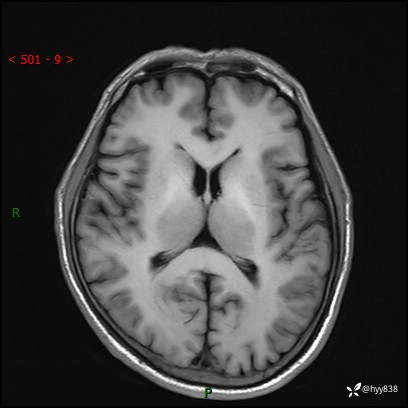

颅脑MRI平扫